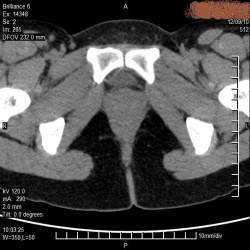

добрый вечер коллеги!друг уролог попросил проконсультировать на сайте, говорит около матки кисту подозревают. Врачи КТ у нас все разъехались,...

Барышня, 25 лет, обследуется по направлению гинеколога.Что скажете?

Мужчина, 43 года, жалуется на боли в области крестца и копчика усиливающиеся в сидячем положении около года. около 2-3х дней назад боли значительно усилились, сидеть не может. при осмотре...